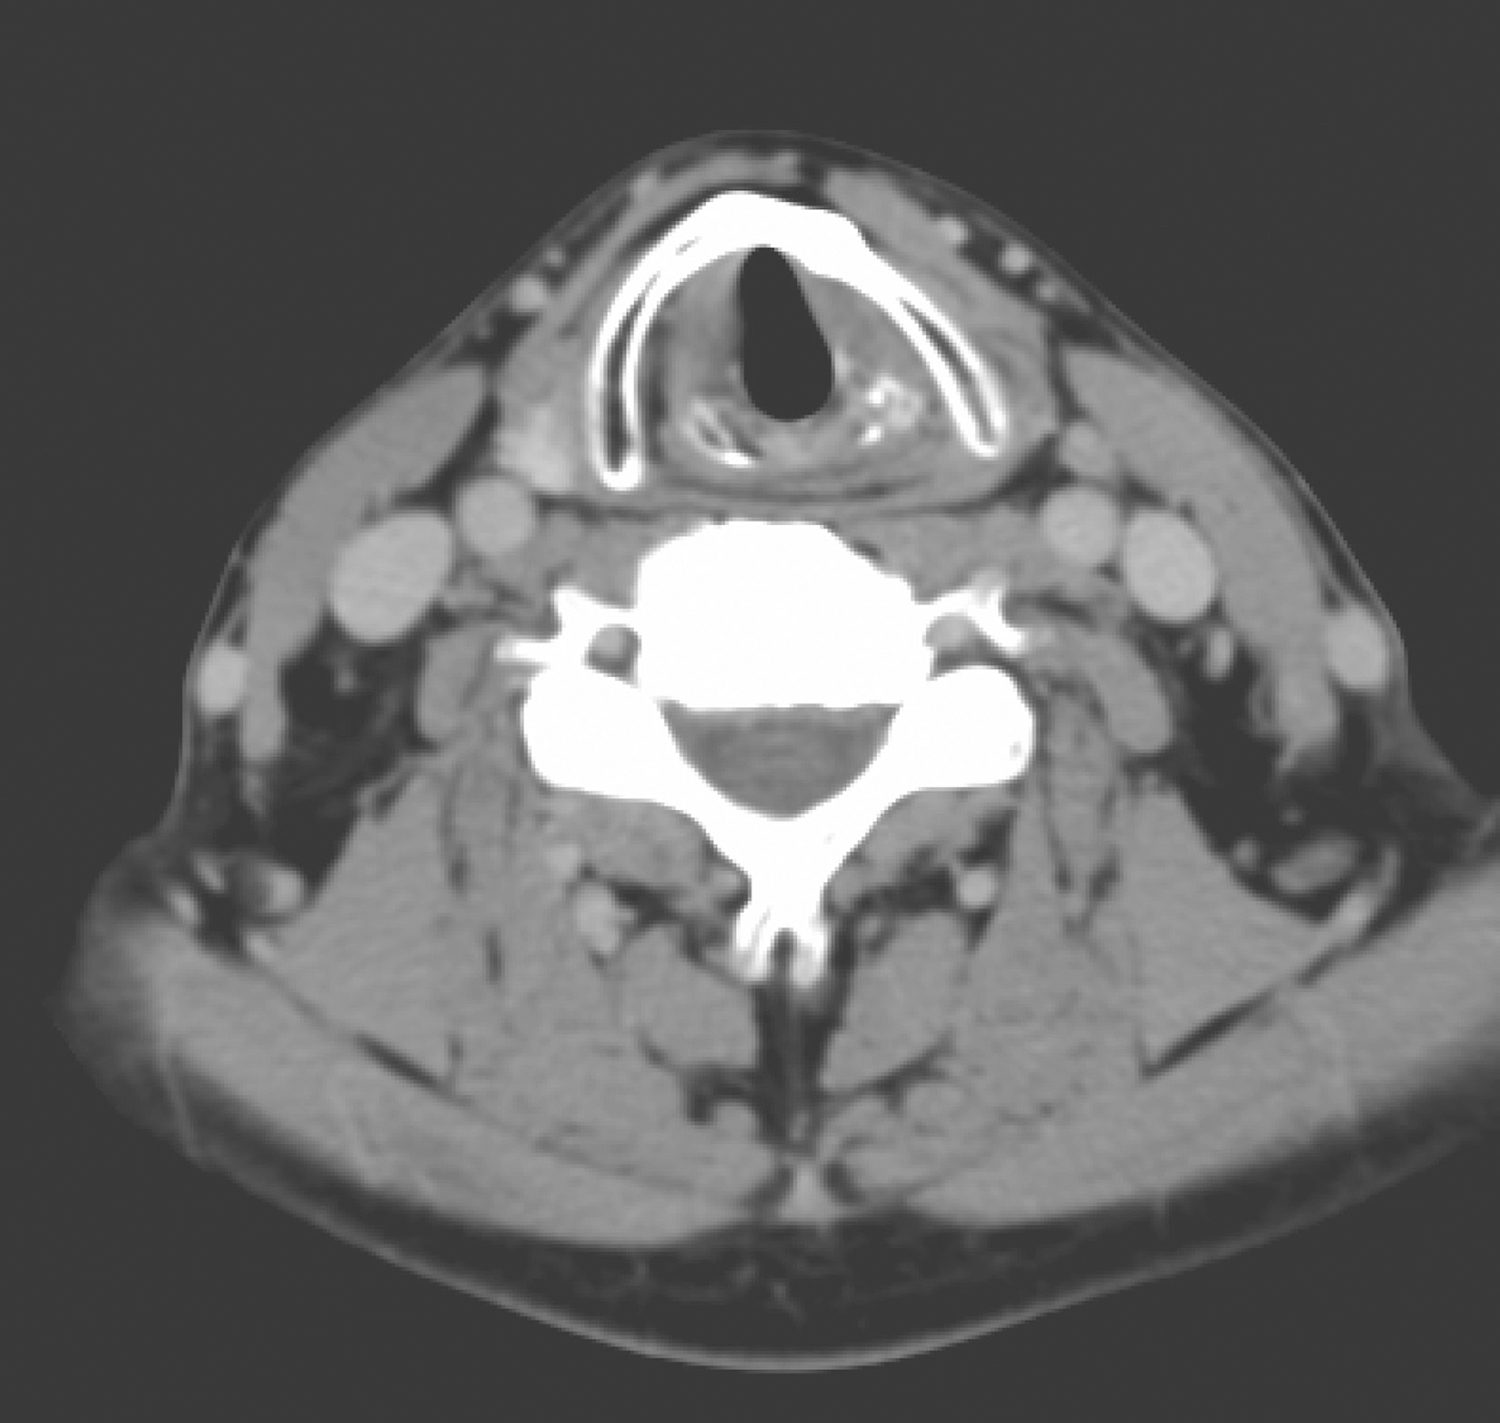

2.2014年12月1日颈胸部强化CT:左侧梨状窝内侧壁、左侧杓会厌皱襞局部软组织增厚,约2cm×2cm,形态不规则,可见强化(图2)。左侧Ⅲ区颈鞘前方可见肿大淋巴结一枚,约2cm大小,轻度强化(图3),余颈部、纵隔未见肿大淋巴结,肺部未见占位病变。

图3左颈部Ⅲ区肿大淋巴结

影像学诊断:

(2)左颈部Ⅲ区肿大淋巴结,转移可能。